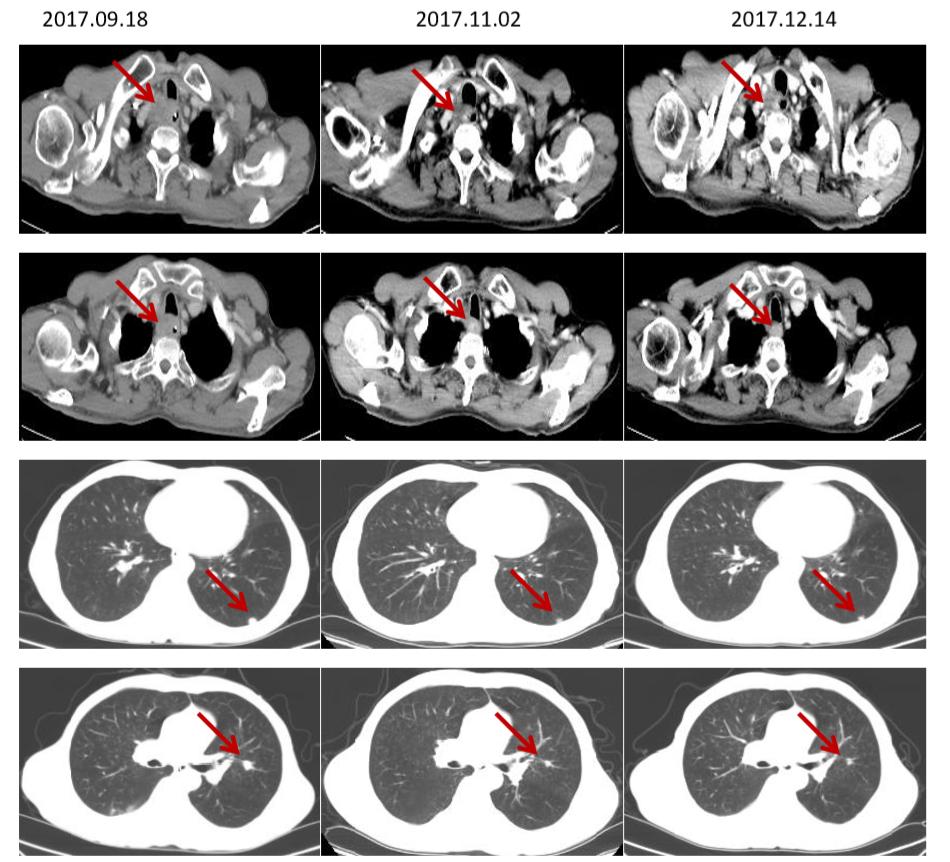

于2017-9-19、2017-10-11、2017-11-3、2017-11-24、2017-12-16、2018-1-12按“紫杉醇+奈达铂”方案化疗6周期,临床疗效评价为PR。

于2018.01.23-2018.03.06在安阳市肿瘤医院行颈部根治性放疗,剂量:60Gy/30d。

2周期复查(2018.08.07)部分肺转移灶较前稍增大(假性进展),4周期及以后食管壁增厚较前好转,肺转移灶较前缩小,临床疗效PR。

CT(脑转移治疗前后食管病灶及肺转移灶对比,部分肺转移灶较前增大)

CT(食管增厚较前明显改善,肺转移灶较前缩小)